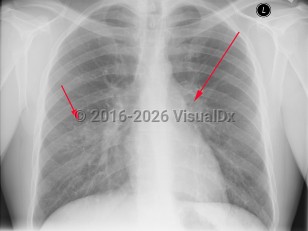

The tubercular bacilli from the infective droplet are taken up by the alveolar macrophages, particularly in the upper and mid-lung zones, which have the highest air flow rates. The breach of the bacteria into the subpleural interstitium causes a local inflammation and consolidation with an exudate and cellular infiltrate. This hallmark of primary pulmonary infection is called the Ghon focus. The bacilli are then rapidly taken up by the mediastinal lymph nodes (hilar and/or paratracheal), resulting in their enlargement and liquefaction, which liberates bacilli that can spread hematogenously throughout the body, seeding different organs. The Ghon focus and the mediastinal lymph node enlargement form the primary or Ranke complex. In most patients, the infection remains latent, being forever contained by the development of cell-mediated immunity that results within 3 weeks to 3 months in a positive skin (tuberculin) test. However, in 5%-10% of patients, mostly within 2-3 years, this initial infection evolves toward active TB. This progression is more common in immunosuppressed states such as AIDS and in children younger than 5 years. While pulmonary TB is the most common form of TB in adults and children, extrapulmonary TB can occur in any age group, although it is more common in younger age groups (eg, tuberculous lymphadenitis).

Symptoms of pulmonary TB are nonspecific and include anorexia, fatigue, anemia, weight loss, fevers, and night sweats. Cough is usually productive, and hemoptysis may occur. Pleural involvement may lead to chest pain and dyspnea. Physical examination findings include rales and signs of consolidation. Auscultation over cavities may reveal amphoric breath sounds (like the sound made by blowing across the mouth of a jar). Signs of pleural effusion may also be found. Pericarditis and pericardial effusion can occur.

The clinical manifestations of TB in HIV-infected patients correlate with the degree of immunosuppression. In general, patients with early HIV present with similar features to those without HIV. Patients with advanced HIV and TB may present with unusual manifestations such as the involvement of middle and lower lobes, negative purified protein derivative (PPD) testing, less cavitary disease, and more frequent extrapulmonary disease, especially lymphadenitis and pleurisy. In these patients, TB can also present with acute respiratory failure and acute respiratory distress syndrome. In older adults, newly acquired pulmonary TB may present with nonresolving pneumonitis of the middle and lower lobes. In countries with a high burden of HIV infection and TB, patients may present with sepsis and organ dysfunction.